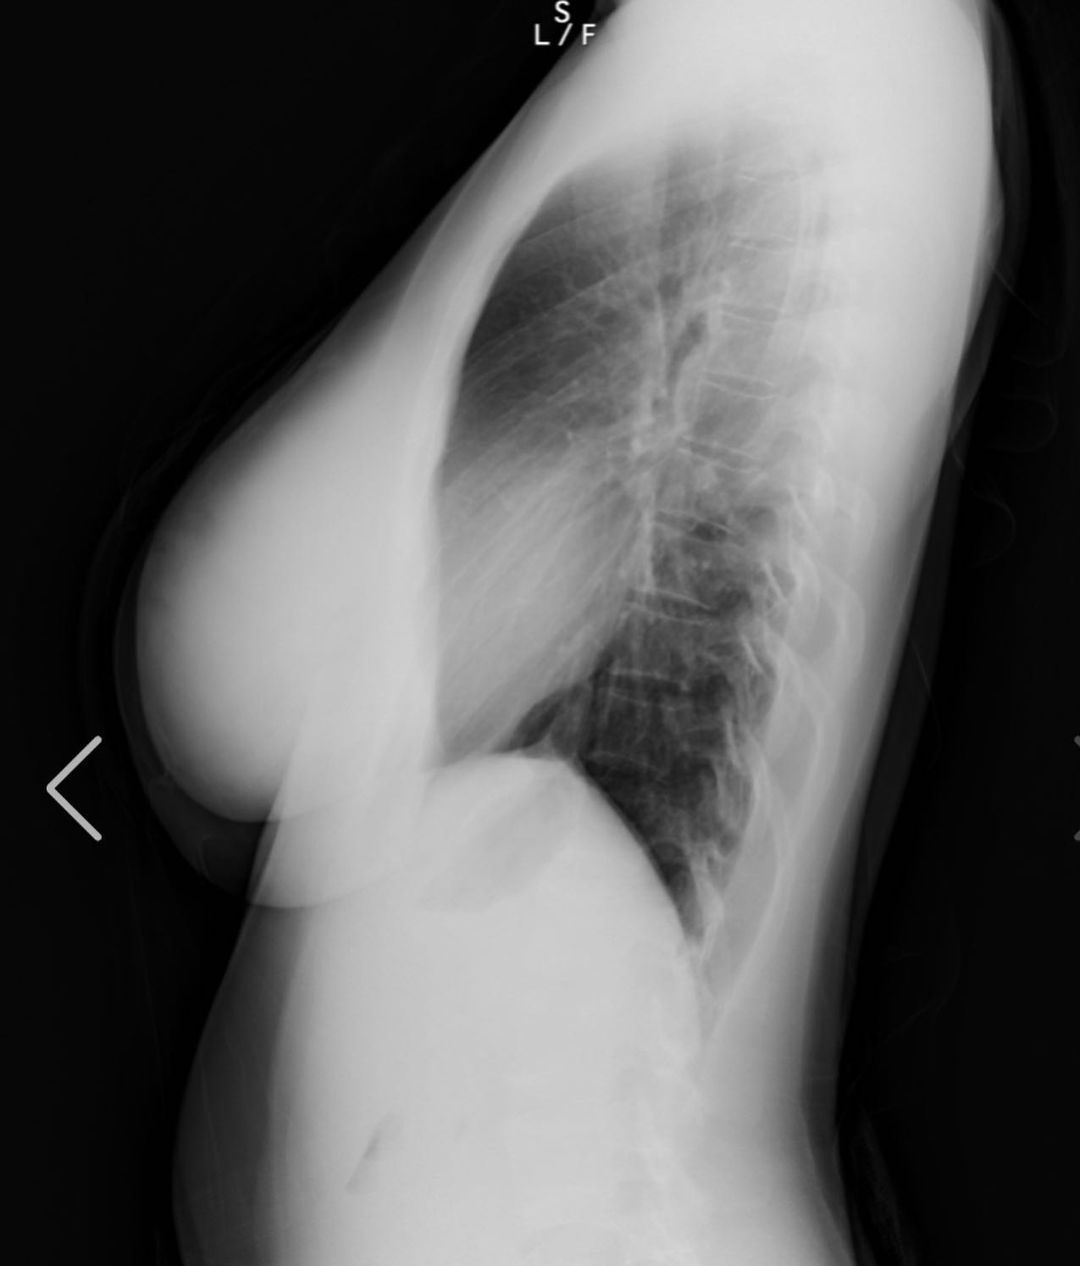

写真は私の胸部レントゲンです!www

裸を通り越して私の骨と脂肪を

見れたあなたには幸運が訪れると

信じてます❤️(私の胸は遺伝です)w